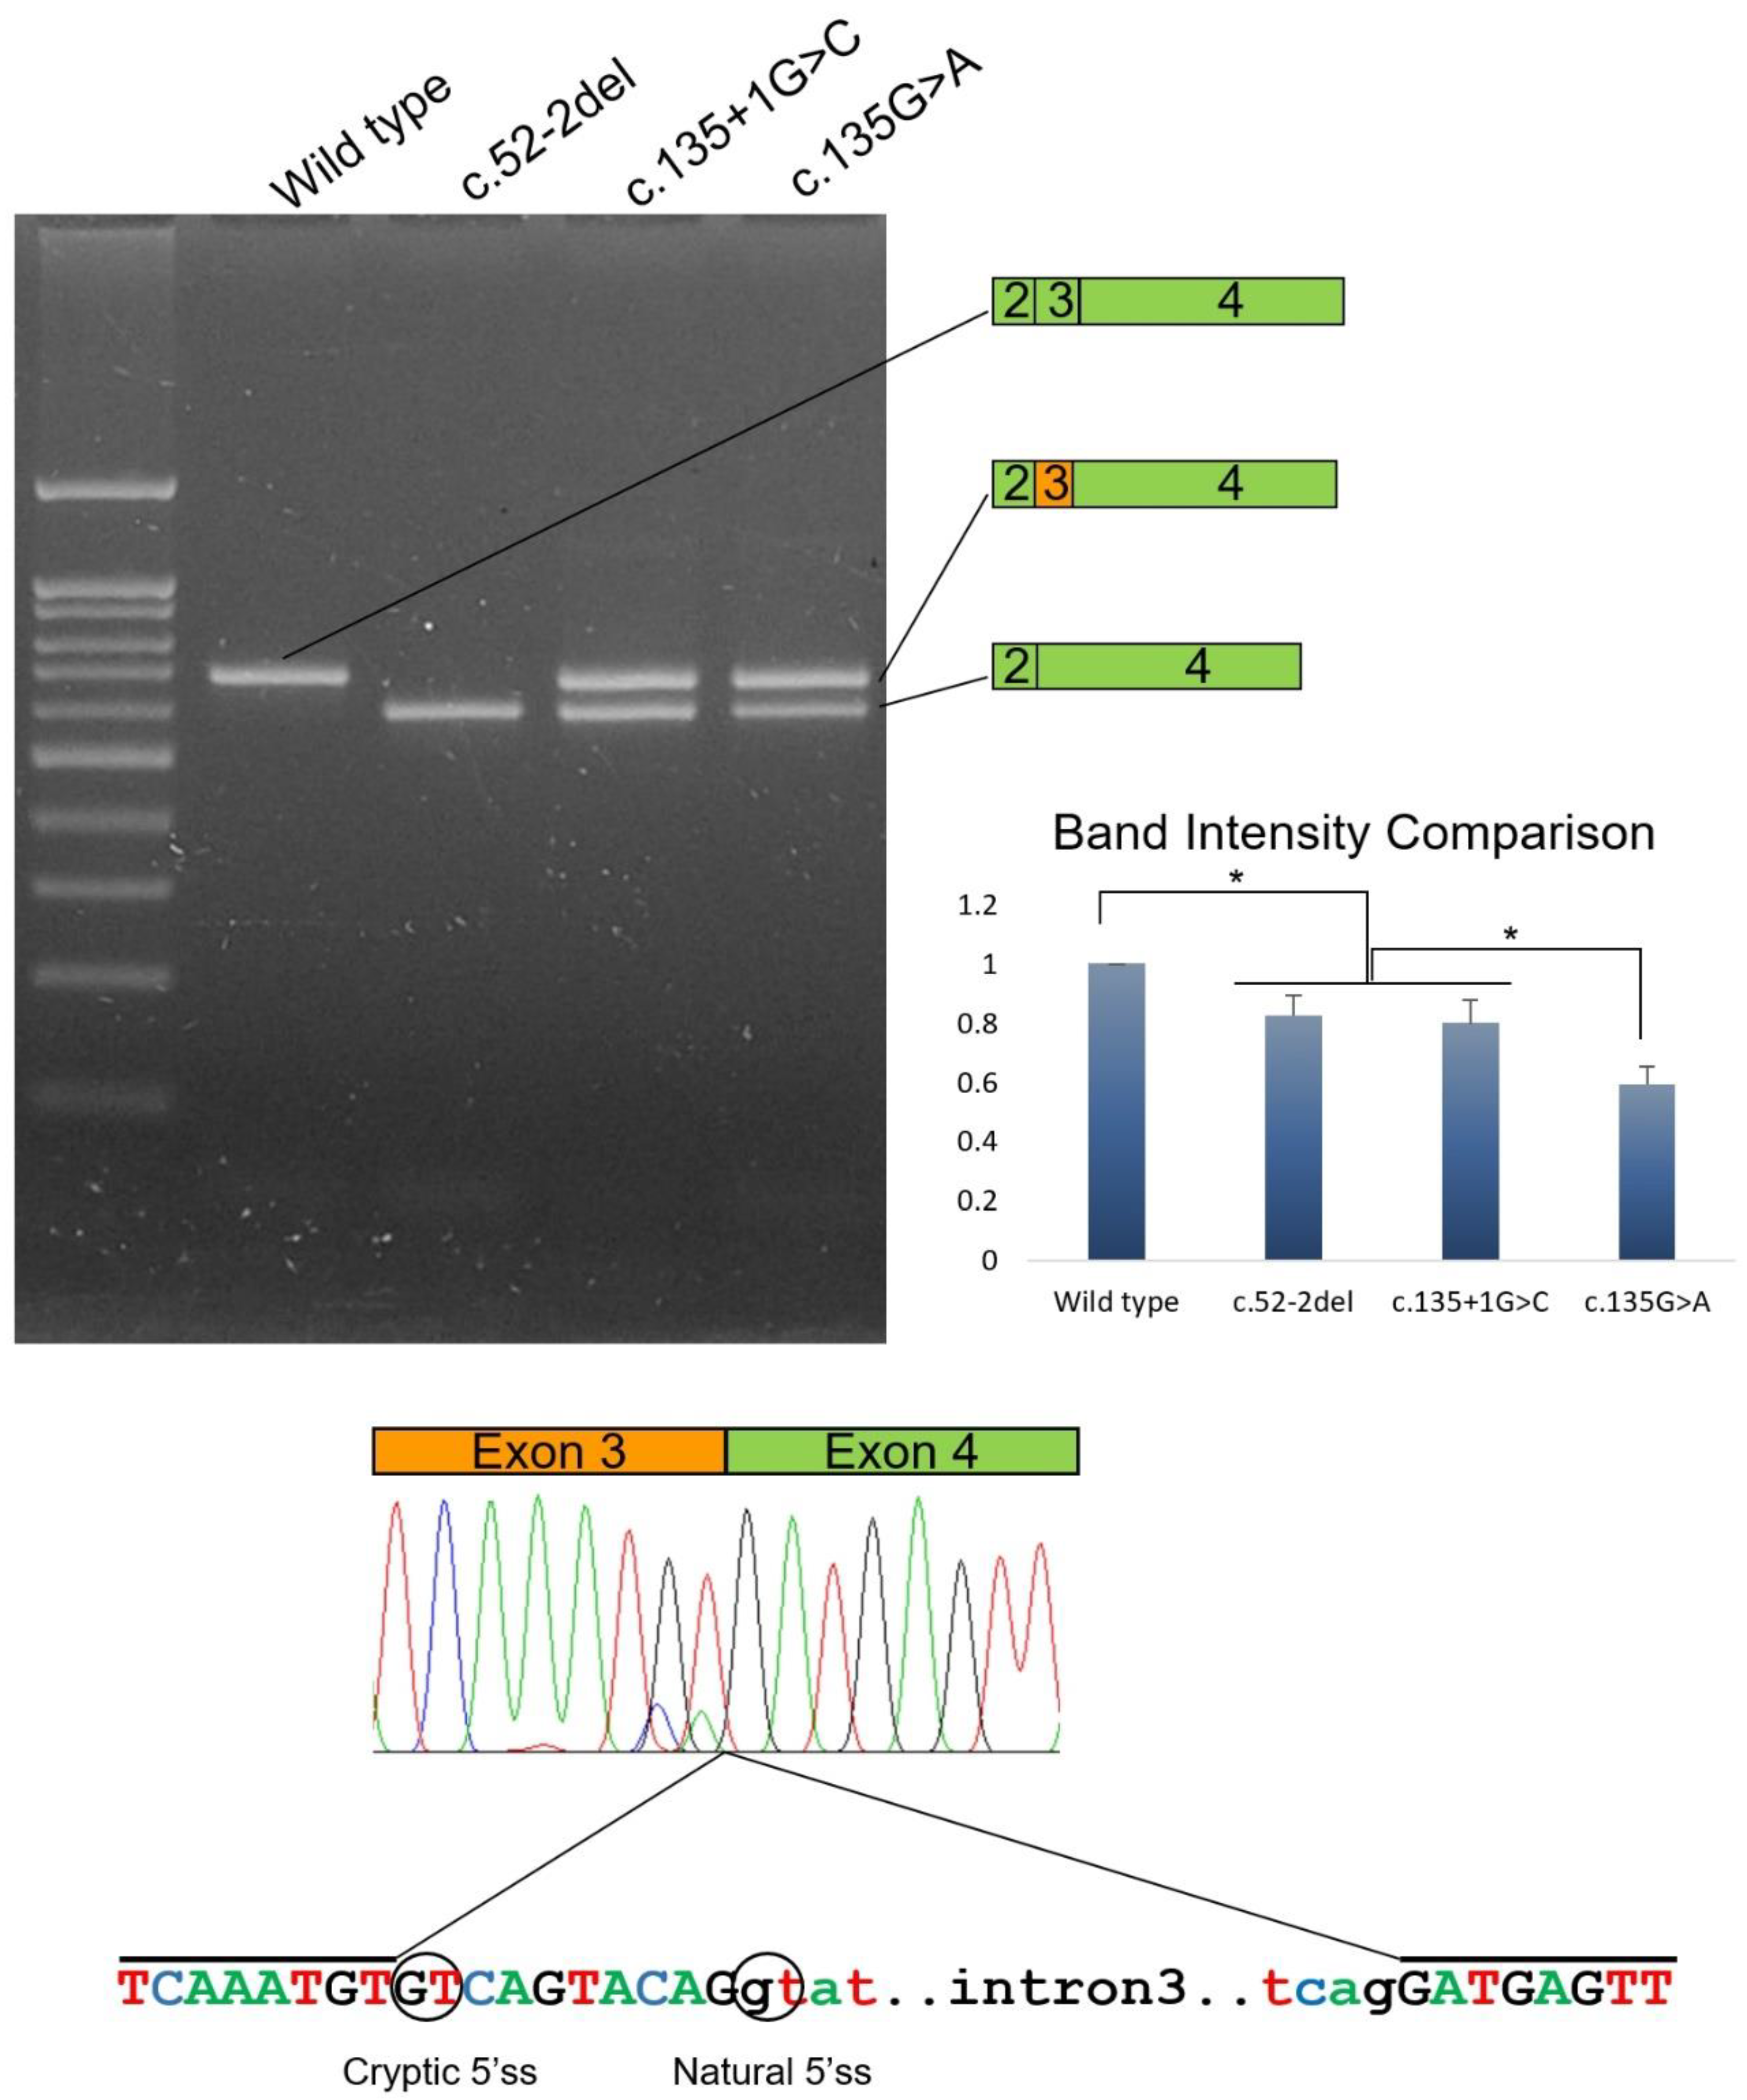

3.4. Identification and Characterization of the Mutations of Family 1

3.5. Identification and Characterization of the Mutations of Family 2

3.6. Identification and Characterization of the Mutations of Family 3